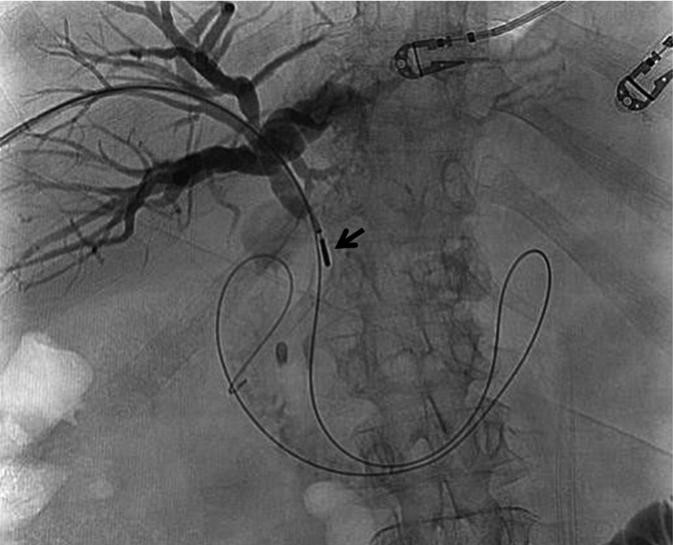

The doctors at Zaragoza University Hospital in Spain applied microwave energy to destroy tumor growth within the main bile duct to reestablish and maintain normal bile flow. A flexible catheter with a microwave antenna tip is inserted into the liver under fluoroscopy into the bile duct with blockages. Once the antenna is positioned in the blockage, microwave energy is applied using preset power, temperature and time durations endocavitary. The antenna is pulled along within the duct with the blockage, and the energy application is repeated until the desired length of the duct is treated. The doctors removed the microwave catheter and verify bile-duct flow with fluoroscopy.  Doctors place resorbable prosthesis, dilation stent balloon, and 5F catheter for 24hrs. No complications were observed. The microwave energy application is controlled with direct temperature feedback from the ablation antenna during the procedure to ensure safety and efficacy.

AveCure® microwave ablation system is successfully treating tumors in bile-duct using a minimally invasive technique, the percutaneous transhepatic cholangiography (PTC) incision through the skin to access the tumor through liver, and patient is left with a small hole in the skin which quickly heals with almost no scar after the procedure.  AveCure® system utilizes a smart antenna in either probe or catheter format and microwave energy controller to select the correct size, temperature, and timer settings appropriate for safe, effective and predictable treatment.